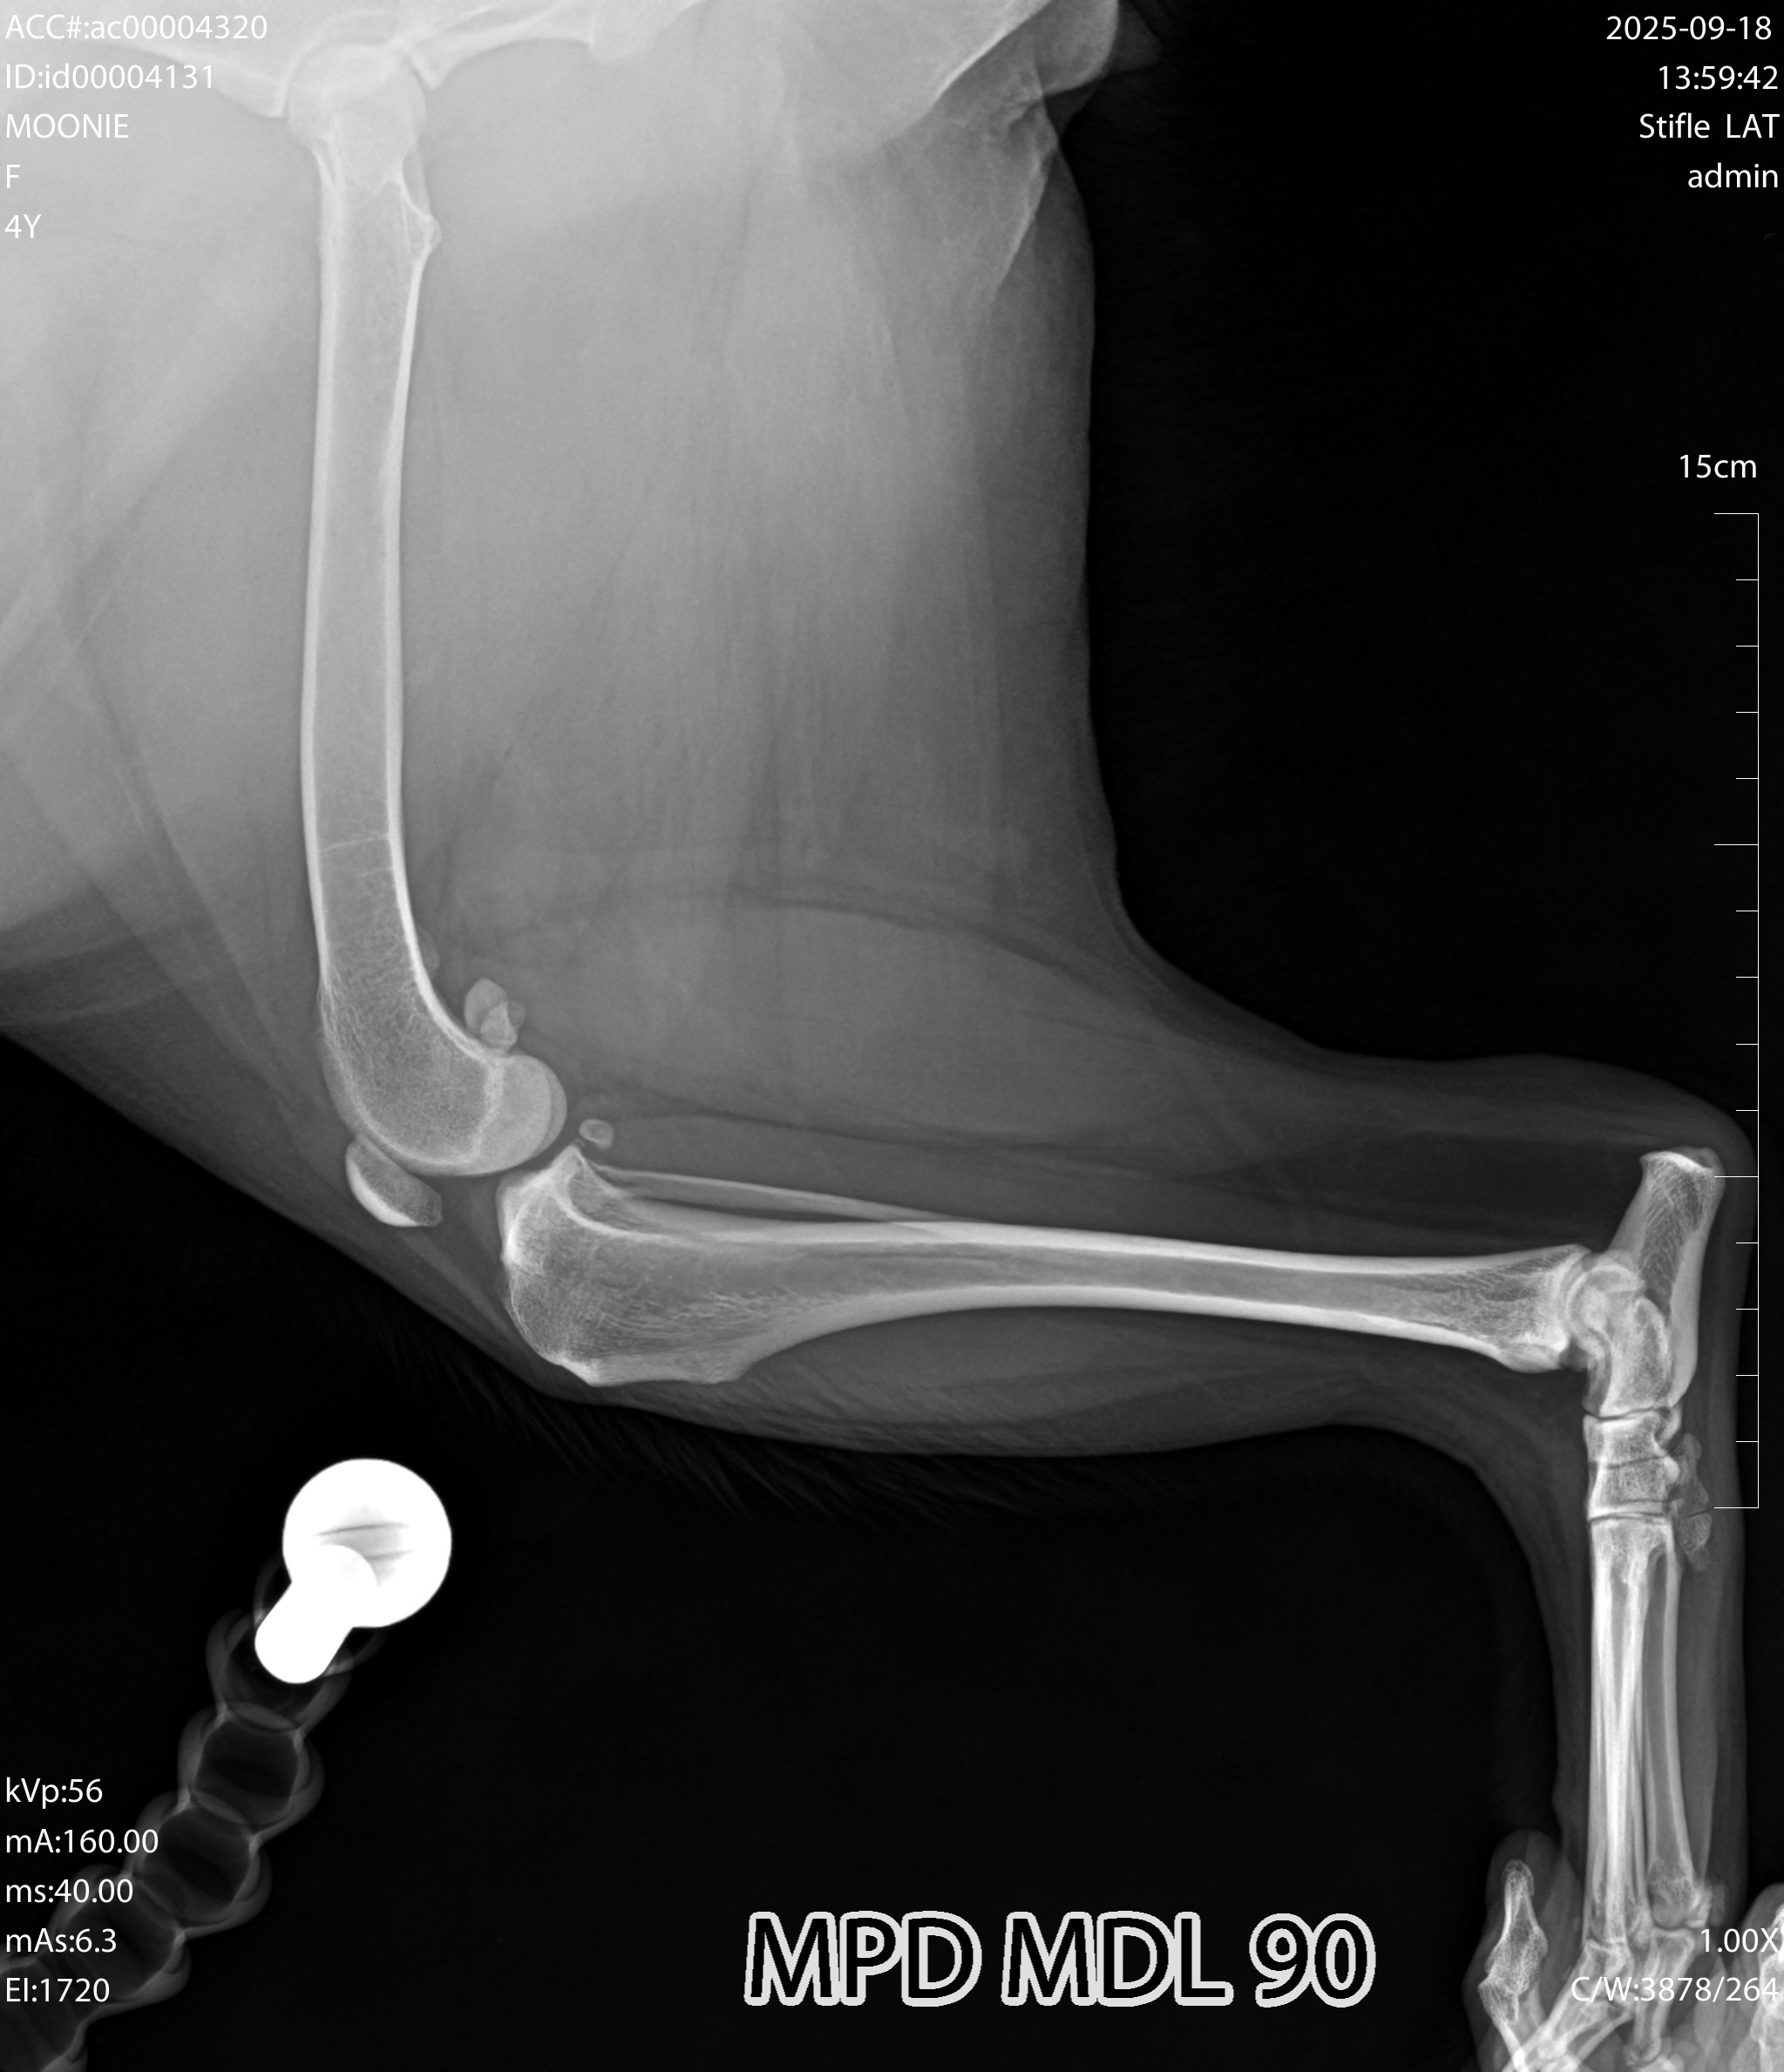

Hello, my name is Giovanna, and I’m raising funds for my beloved dog, who desperately needs ACL surgery. She is more than a pet ❤️; she is my family. She sleeps by my side every night and has been companion for four years. I want to give her the healthy, pain-free life she deserves.

I live in Imperial CA, and unfortunately, there are no veterinary specialists here who can perform the surgery my dog needs. My only option nearby was to try clinics in Mexicali, Mexico. In the past, when I lived in San Diego, I had good experiences in Tijuana, so I trusted it would be the same. Sadly, this time I was scammed. I’ve already spent about $500 on consultations, medications, x-rays, and bloodwork, but the clinics kept canceling appointments and surgeries, and my dog still hasn’t received the care she needs.

My dog is still young, only four years old, and I pray she has many more happy years ahead. Any donation, big or small, will go directly toward her surgery and recovery. Your support means everything to me, and it would relieve the heavy stress of not knowing if I can give her the care she needs.